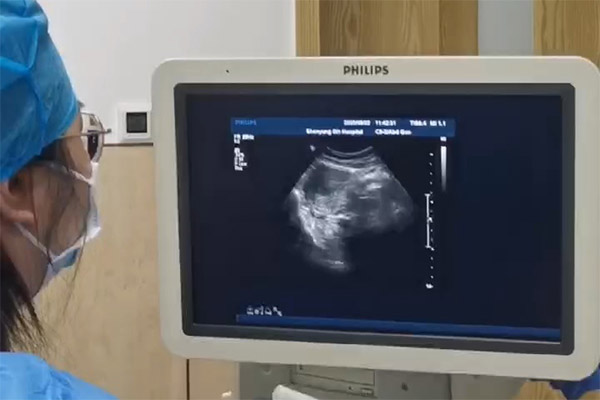

▲患者术中超导可视画面